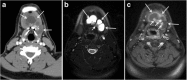

Focal and diffuse thyroid abnormalities are commonly encountered during the interpretation of computed tomography (CT) exams performed for various clinical purposes. These findings can often lead to a diagnostic dilemma, as the CT reflects the nonspecific appearances. Ultrasound (US) examination has a superior spatial resolution and is considered the modality of choice for thyroid evaluation. Nevertheless, CT detects incidental thyroid nodules (ITNs) and plays an important role in the evaluation of thyroid cancer. In this pictorial review, we cover a wide spectrum of common and uncommon, incidental and non-incidental thyroid findings from CT scans. We also discuss the most common incidental thyroid findings, best practices for their evaluation, and recommendations for their management. In addition, we explore the role of imaging in the assessment of thyroid carcinoma (before and after treatment) and preoperative thyroid goiter, as well as localization of ectopic and congenital thyroid tissue.

Teaching points: • Thyroid disorders tend to have non-specific CT appearances. • ITNs are common on neck CT. • ITN management depends on nodule size, age, health status, lymphadenopathy, and invasion. • CT is used in assessment of cancer extension, mass effect, invasion, and recurrence. • CT plays a role in preoperative planning in patients with symptomatic goiter.